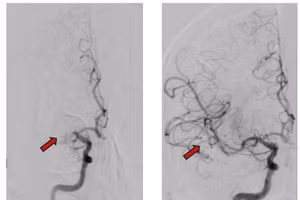

GD&TĐ - Bệnh nhân Nga đột quỵ được cứu sống sau khi chuyển cấp cứu từ Nha Trang (Khánh Hòa) vào Bệnh viện Nhân Dân 115.